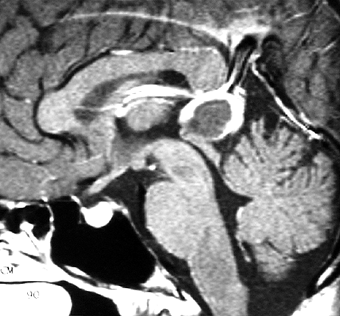

成人女性の松果体細胞腫で充実性腫瘍です。多少凹凸がありますがだいたい楕円形。中脳水道が閉塞して軽度の水頭症(頭の中に髄液が溜まる)になってきています。急性水頭症で急変して意識障害になることがありますので,迷わず摘出するか,第3脳室開窓術 ETVをしてから経過観察します。